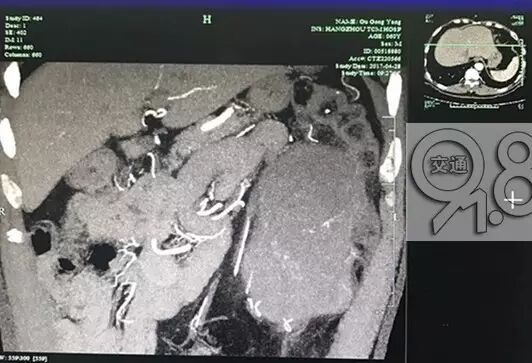

经过CT检查发现,大伯左侧长了一个腹膜后脂肪肉瘤。杭州市中医院泌尿外科黄亚胜副主任坦言:大伯的肿瘤长在左胃下方,有三四斤重,婴儿头那么大,选择手术治疗。这是生长到一定程度,才会出现的症状。切开这个肿瘤,发现里面都是些脂肪样的物质。”